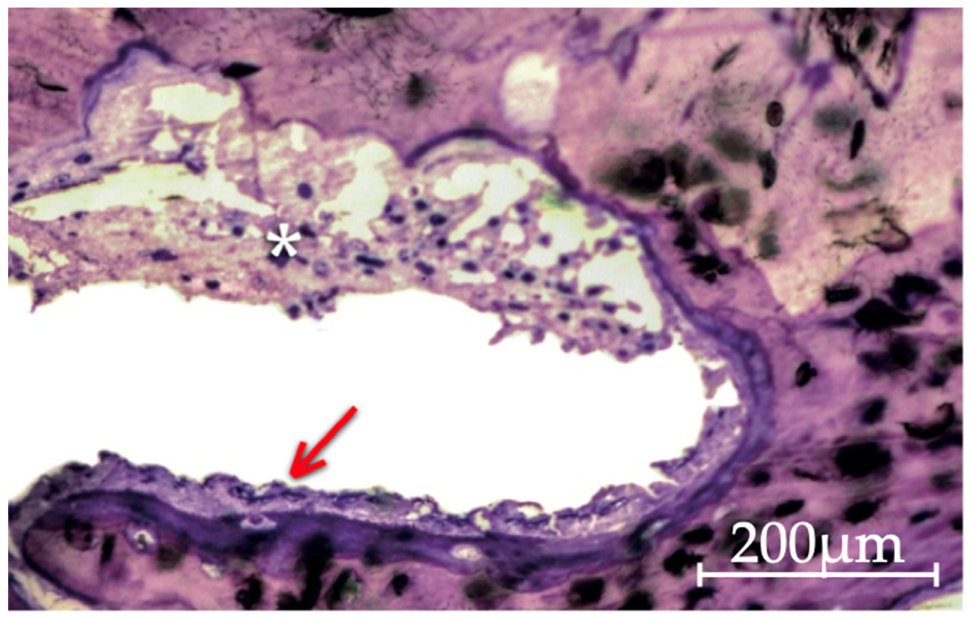

3.2.4. Putty and Gel 40 Groups

3.3. Quantitative Histomorphometric Analysis

3.3.1. Analysis within Each Group